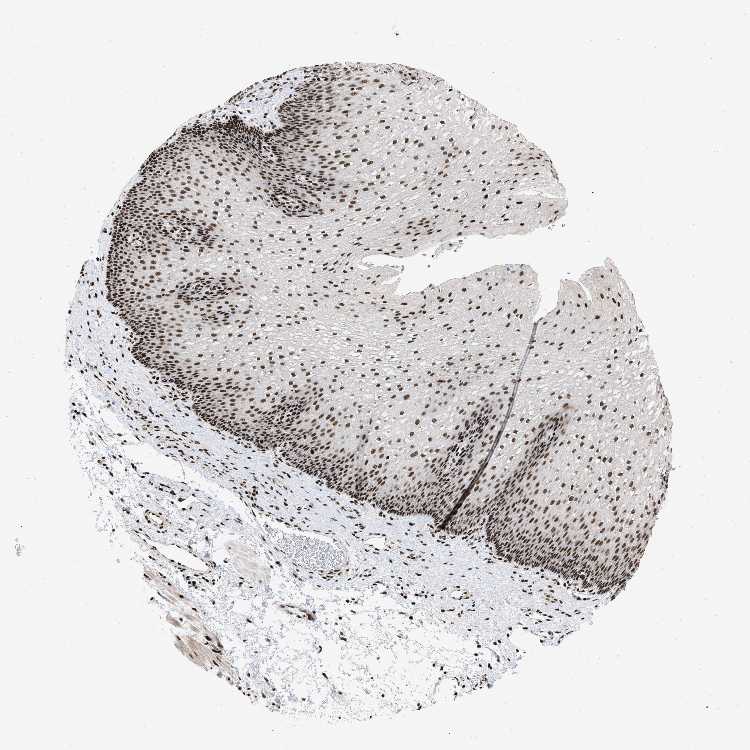

ESOPHAGUS - Antibody stainingi

Antibody staining in the annotated cell types in the current human tissue is reported as not detected, low, medium, or high, based on conventional immunohistochemistry profiling in selected tissues. This score is based on the combination of the staining intensity and fraction of stained cells.

Each image is clickable and will lead to virtual microscopy that enables deeper exploration of all samples and also displays staining intensity scores, fraction scores and subcellular localization as well as patient and tissue information for each sample.

Antibody HPA019150Antibody CAB003803

Squamous epithelial cells HighHigh